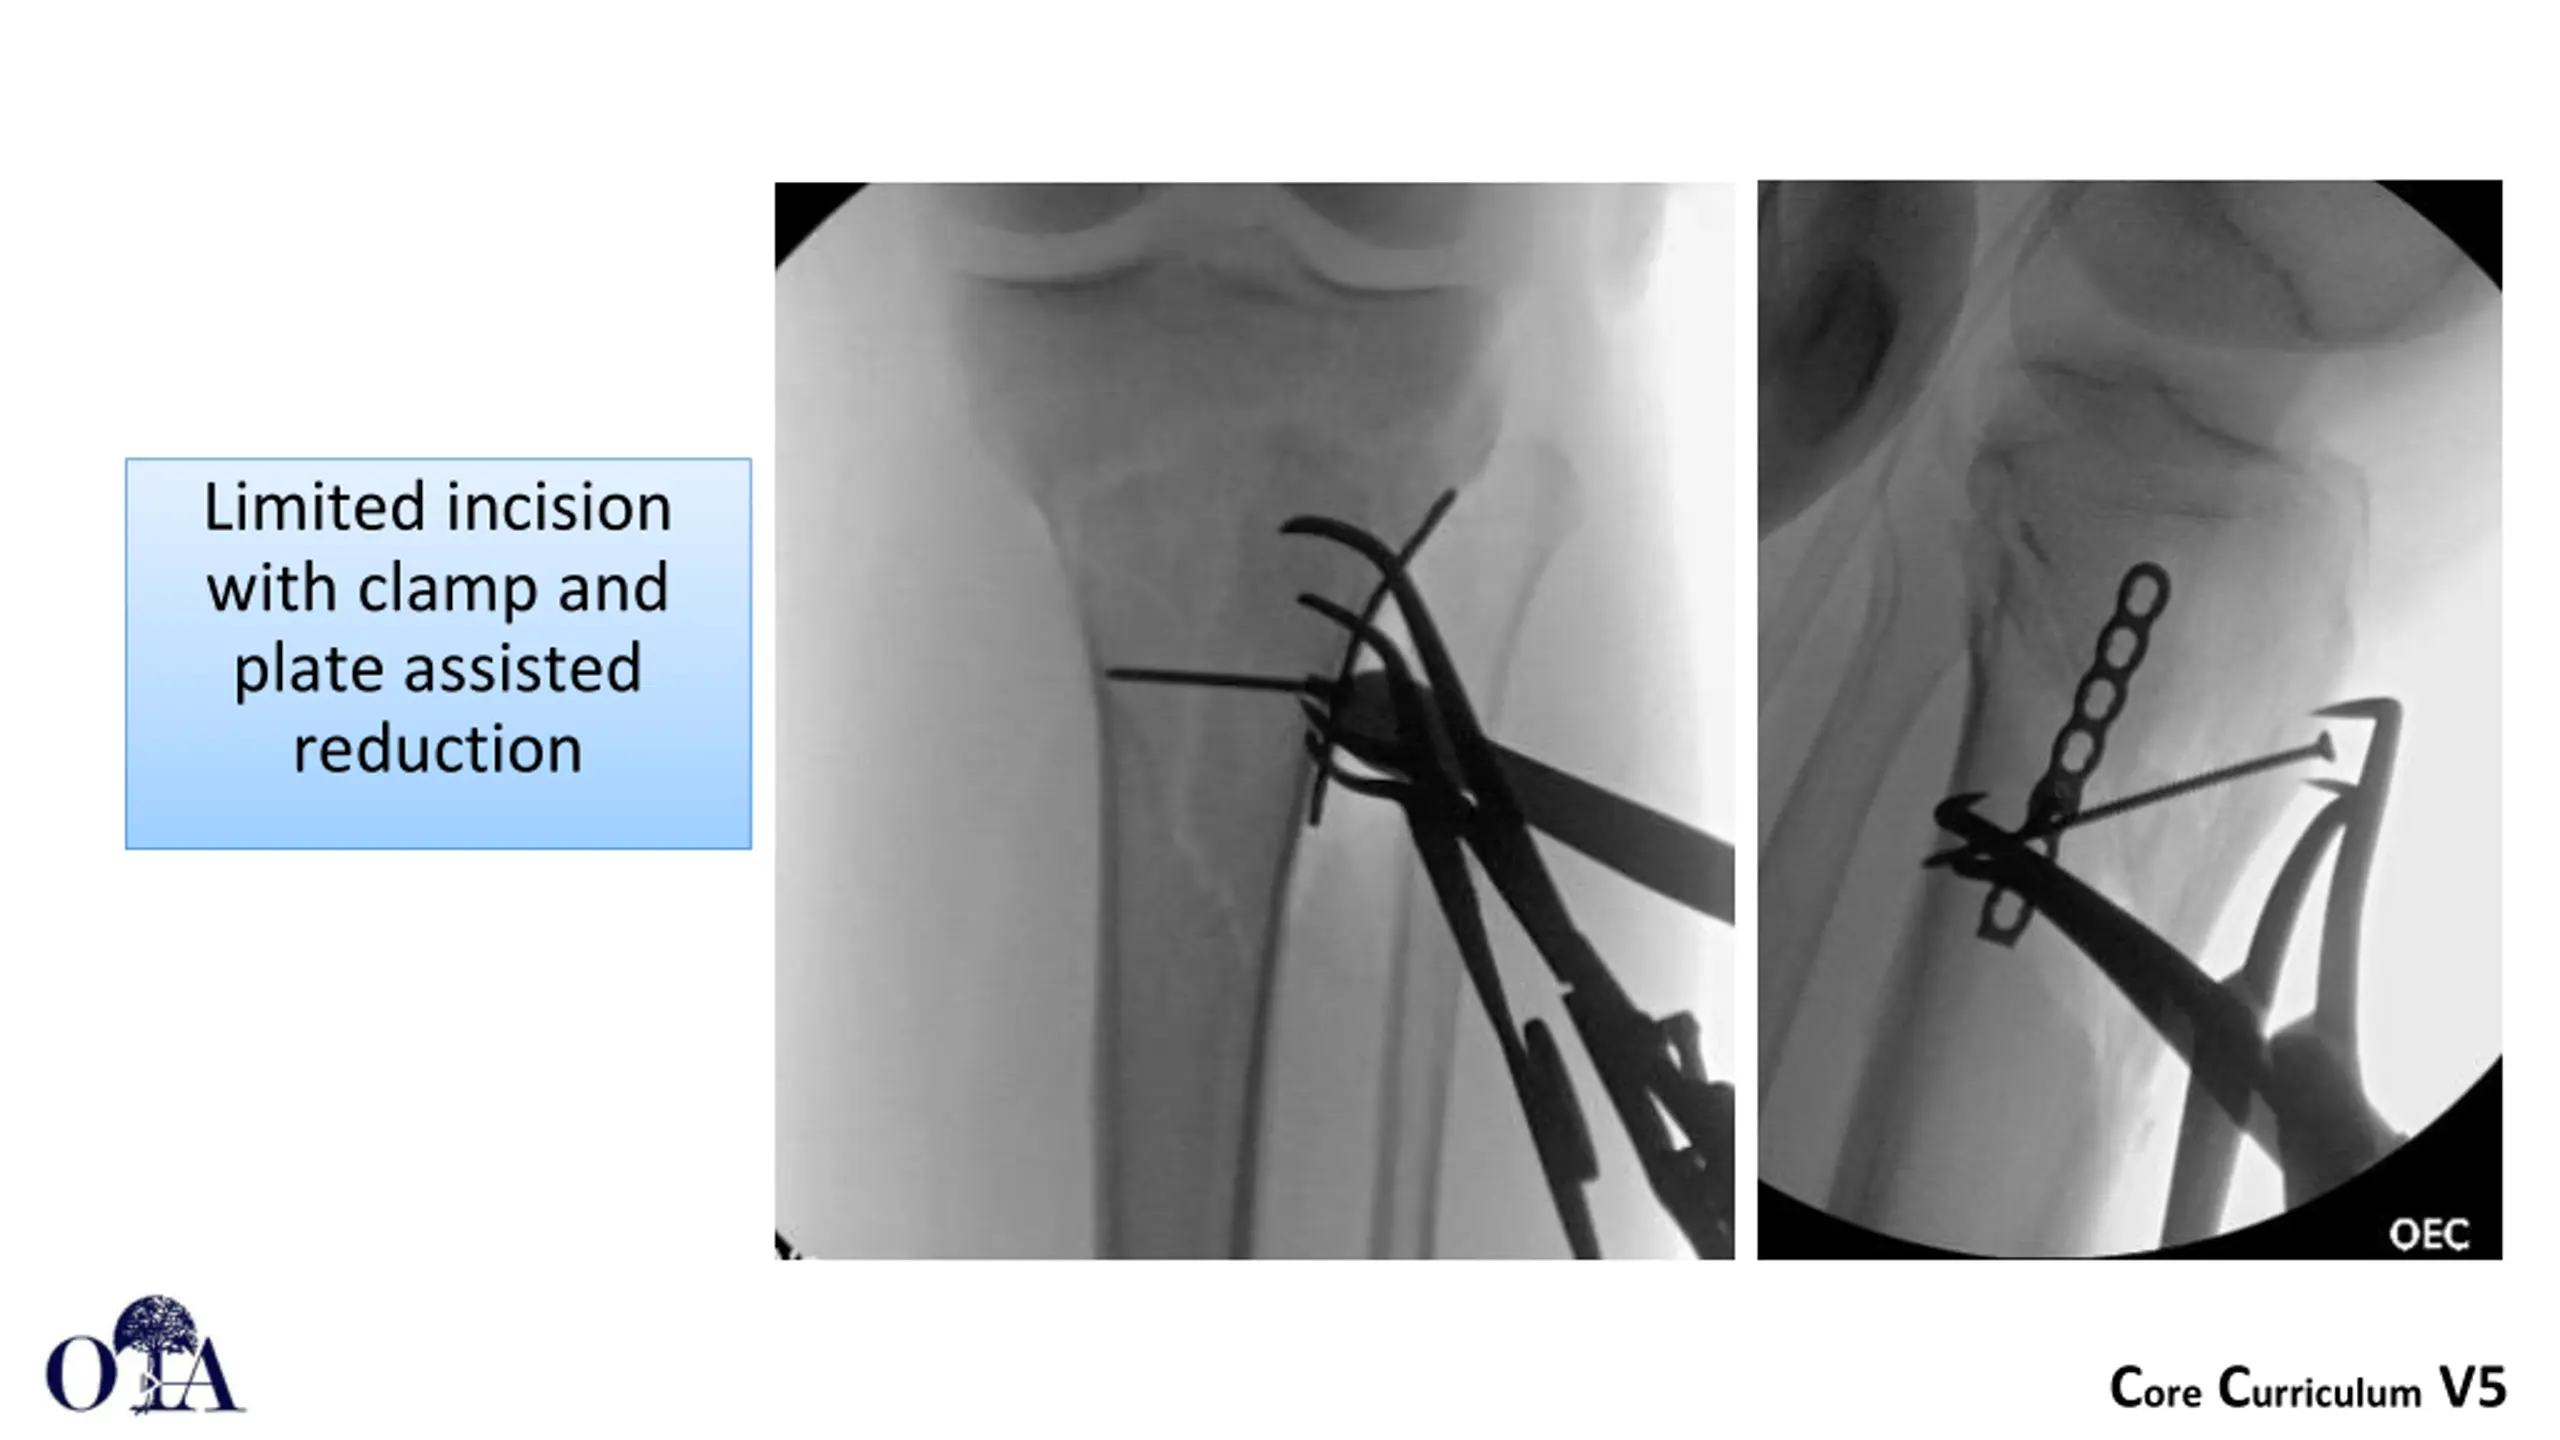

Limited incision with clamp and plate assisted reduction Core Curriculum V5